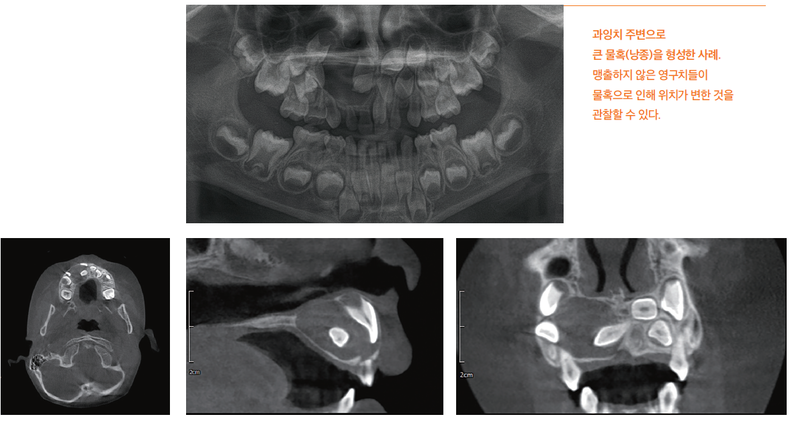

더 나아가 과잉치 주변에는 물혹인 낭종이 생길 수 있으며, 이 낭종이 커지면 주변 뼈를 파괴하고 인접한 치아들을 밀어내어 영구치의 변위를 일으킬 수 있습니다.